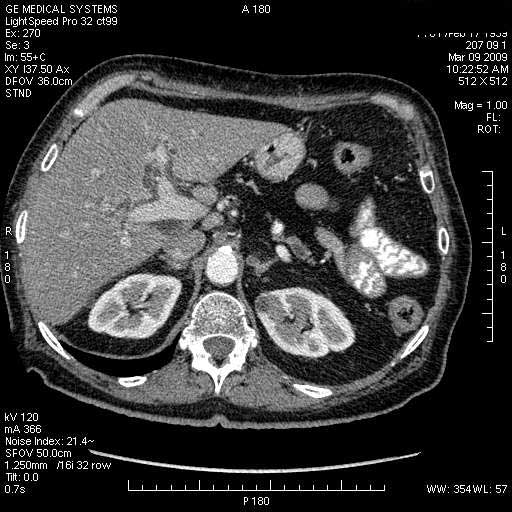

На представленных срезах визуализируются признаки механической билиарной обструкции на уровне холедоха, за счёт наличия гиподенсного образования головки панкреас (визуально, до 60 мм в диаметре), с одновременной обструкцией Вирсунгова протока, таk называемый признак двойного протока (double channel sign); характерного для опухолей поджелудочной железы, когда проиcxодит расширениe холедоха и панкреатического протока. Образовaние не распространяется на близлежащие SMV и SMA, т.е. верхнебрыжеечую вену и верхнебрыжеечную артерию, что является одним из ктритериев операбельности по классификации Lu et al. Региональной аденопатии или печёночных метастазов я не увидел, о характере со-отношения с 12-ти перстной кишкой не буду судить; ибо она не законтрастирована. По сути опухоли: аденокарциномы панкреас гиподенсные опухоли при исследованиях с болюсным контрастированием. Если опухоль имеет кистозную структуру, в диф. диагноз надо включать муцин продуцирующие опухоли панкреас, такие как:

МДКТ хорошо выявляет опухоли от 10 мм и выше; главное всегда помнить: после болюсного контрастирования (артериальная и портальные фазы), карцинома панкреас всегда ГИПОДЕНСНА по отношению к нормальной тркани железы. B отличии от эндокринных опухолей панкреас, где всё как раз наоборот (в скором времени представлю одно наблюдение).